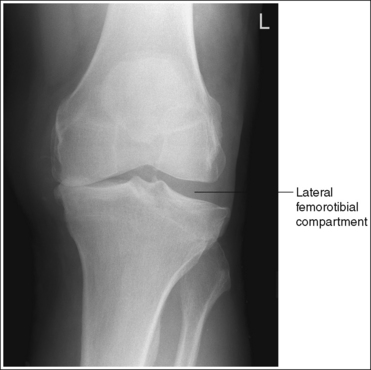

• Analysis of joint space narrowing. On an AP knee projection with adequate positioning, joint space narrowing is evaluated by measuring the medial and lateral aspects of the knee joint, which are also referred to as compartments. The measurement of each of these compartments is obtained by determining the distance between the most distal femoral condylar surface and the posterior condylar margin of the tibia on each side. Comparison of these measurements with each other, with measurements from previous images, or with measurements of the other knee determines joint space narrowing or a valgus or varus deformity. In a valgus deformity the lateral compartment is narrower than the medial compartment; in a varus deformity the medial compartment is narrower (see Images 56 and 57). Precise measurements of the compartments are necessary to ensure early detection of joint space narrowing and are best obtained when the knee joint space is completely open. If an inaccurate central ray angulation was used for an AP knee projection, the knee joint is narrowed or obscured, the intercondylar eminence and tubercles are foreshortened, and the tibial plateau is demonstrated.

IMAGE 57

The lateral knee compartment is narrower than the medial knee compartment. The patient's knee demonstrates a valgus deformity.

The medial knee compartment is narrower than the lateral knee compartment. The patient's knee demonstrates a varus deformity.